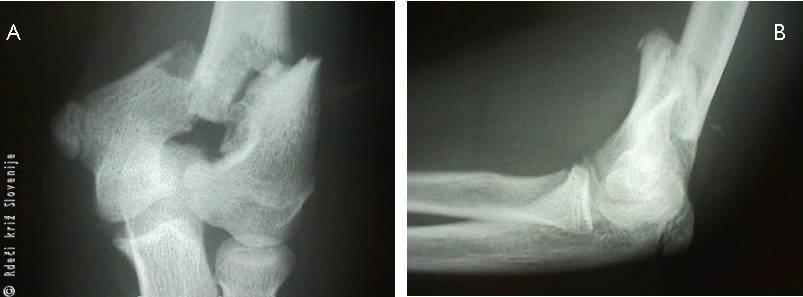

Slika 10

Na prednji (A) in stranski (B) rentgenski sliki je viden znotrajsklepni zlom spodnjega dela nadlahtnice v obliki črke Y.